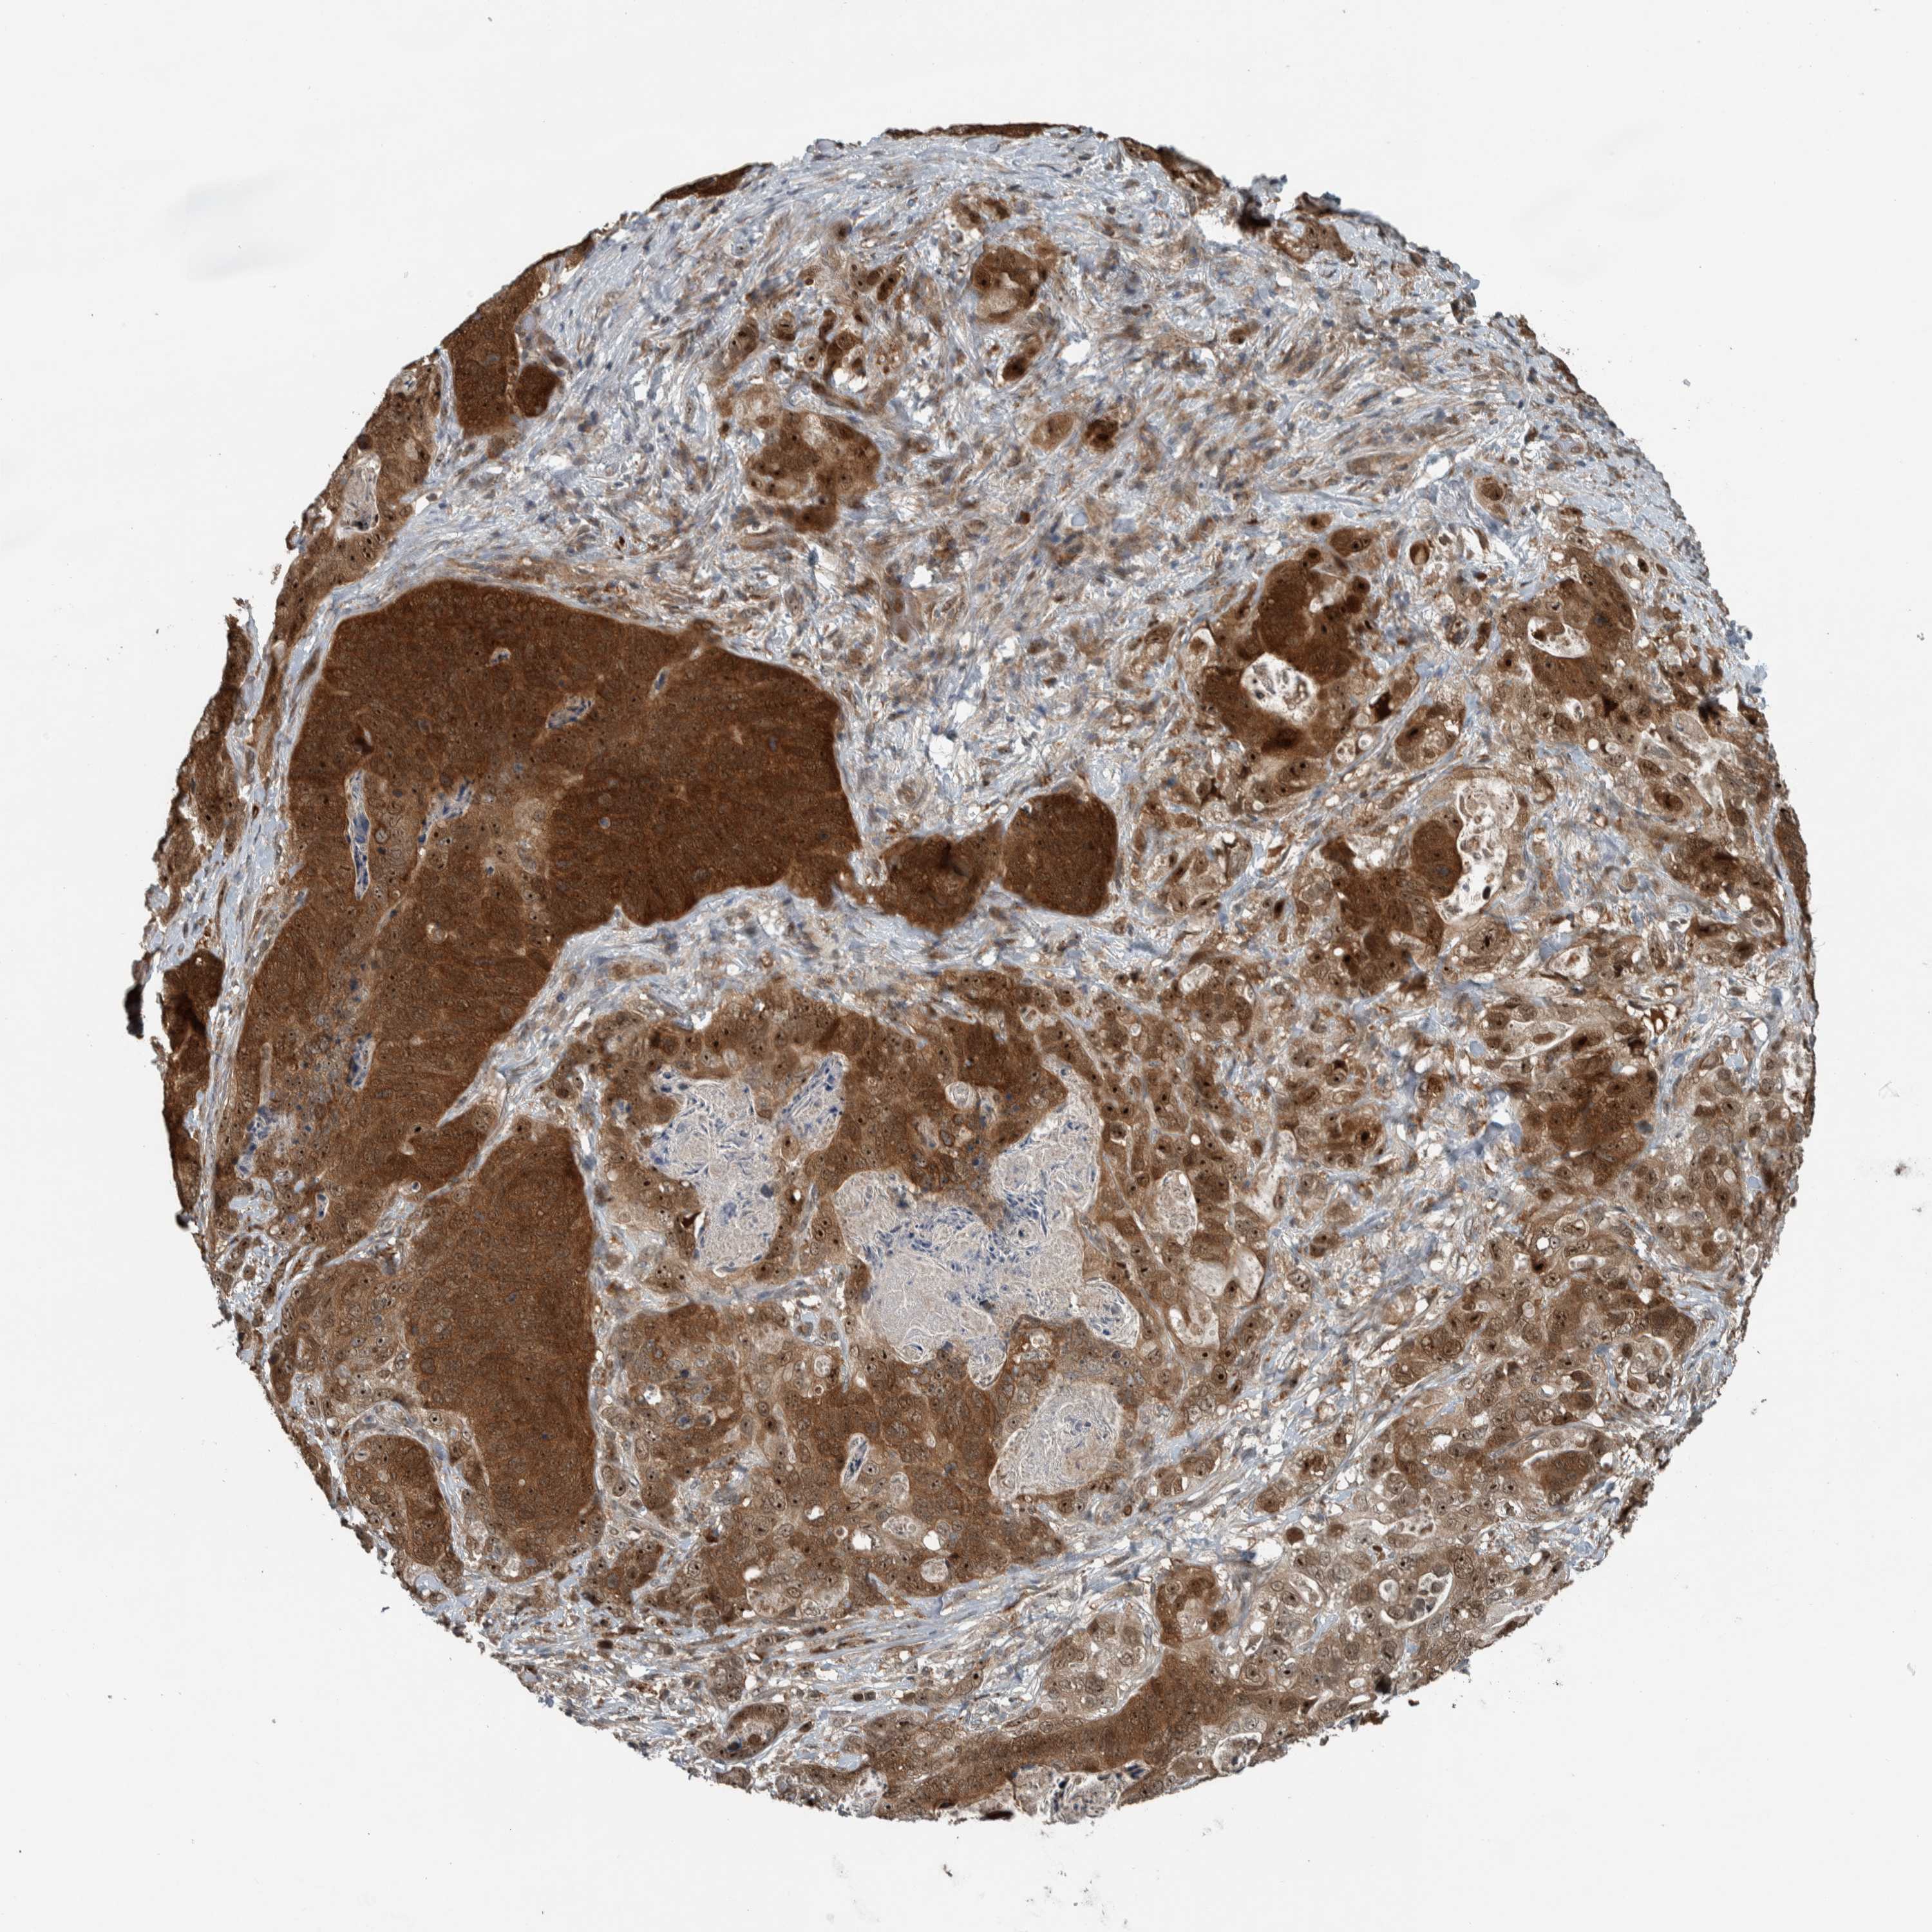

STOMACH CANCER - Protein expressioni

A mouse-over function shows sample information and annotation data. Click on an image to view it in a full screen mode. Samples can be filtered based on level of antibody staining by selecting one or several of the following categories: high, medium, low and not detected. The assay and annotation is described here.

Note that samples used for immunohistochemistry by the Human Protein Atlas do not correspond to samples in the TCGA dataset.

Antibody stainingi

Antibody staining in the annotated cell types in the current human tissue is reported as not detected, low, medium, or high, based on conventional immunohistochemistry profiling in selected tissues. This score is based on the combination of the staining intensity and fraction of stained cells.

Each image is clickable and will lead to virtual microscopy that enables deeper exploration of all samples and also displays staining intensity scores, fraction scores and subcellular localization as well as patient and tissue information for each sample.

Antibody HPA018402

Antibody HPA023959

Staining

High

Medium

Low

Not detected

Intensity

Strong

Moderate

Weak

Negative

Quantity

>75%

75%-25%

<25%

None

Location

Nuclear

Cytoplasmic/membranous

Cytoplasmic/membranous,nuclear

Adenocarcinoma, NOS